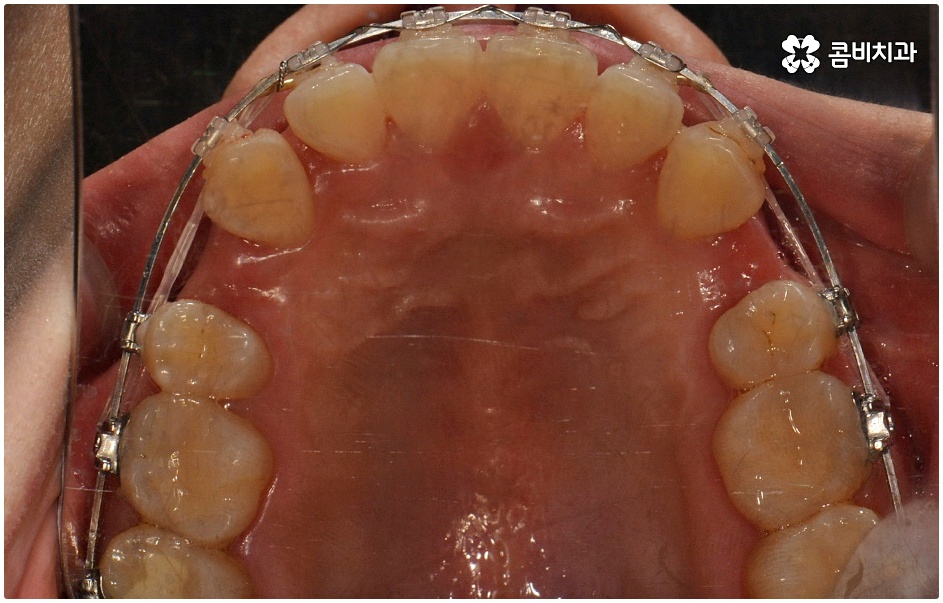

치료를 위해서는 입을 안쪽으로 넣기 위한 공간을 확보해야 하므로 보통 위아래 소구치 총 4개의 치아를 발치하여 그 공간을 활용해 튀어나온 치아와 잇몸을 전체적으로 뒤로 이동시키는 방법을 사용하나 최근에는 미니스크류, 치간 삭제 등의 방법을 이용하여 비발치 교정을 진행하기도 하니 먼저 자신의 상황을 꼼꼼하게 살펴보고 부정 교합의 원인과 정도부터 정확하게 파악하는 것이 필요한 거에요.